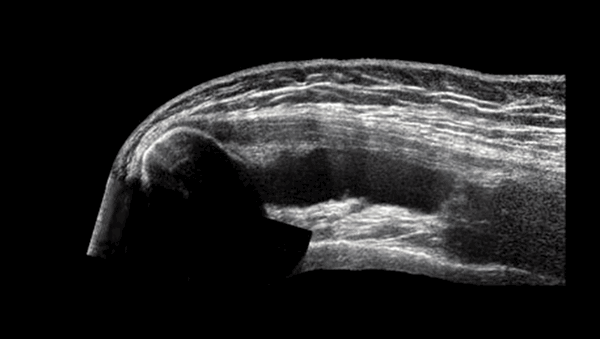

Что лучше УЗИ, КТ или МРТ плечевого сустава?

Врач назначает процедуру исходя из особенностей клинического случая. УЗИ применяют с целью экспресс-диагностики. Изображения, полученные с помощью ультразвука, недостаточно четкие, чтобы поставить точный диагноз. Метод малоинформативен на ранних этапах развития дегенеративно-дистрофических заболеваний. УЗИ плечевого сустава целесообразно при необходимости быстро оценить последствия травмы или исключить осложнения, или в случае противопоказаний у пациента к другим методам диагностики.

УЗИ плеча

Компьютерная томография является быстрым и информативным исследованием. Однако эта диагностическая процедура предпочтительна при подозрениях на переломы, гематомы и кровоизлияния. По фото, полученным при КТ, можно оценить контуры и плотность костной ткани, а вот более рыхлые структуры невозможно разглядеть в достаточной для постановки диагноза мере. Метод применяют с целью быстрой диагностики переломов или е если пациент страдает от острой боли, поскольку исследование длится всего несколько минут.

МРТ считают особенно информативной процедурой при суставных патологиях. Методика безопасна (имеет минимум противопоказаний и не несет лучевой нагрузки), занимает мало времени. При помощи МРТ можно выявить заболевания плечевого сустава на самых ранних этапах их развития.